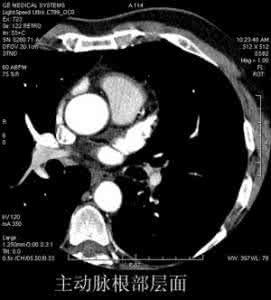

1、主动脉根部层面

相当于心腰下部,范围从左心房上部到右心房、右室上部水平。升主动脉根部已位于纵隔中央,左前方为肺动脉干,构成纵隔左前缘。右心房构成纵隔右缘前部。主动脉根部的后方是左心房,食管紧贴左心房后部,食管后侧方为奇静脉。降主动脉位于食管的左后部,椎体左缘。此外,在左心房上部平面的图像上,可见两侧上肺静脉,在右心房、右心室中部平面可见两侧下肺静脉。